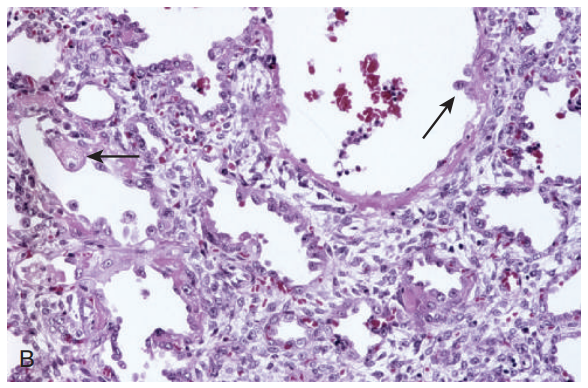

增生期(proliferative stage):第一周后,以纤维母细胞增生和Ⅱ型肺泡上皮增生为特征。病变最终可导致肺间质纤维化和支气管周围纤维化。

43e1bdc91d6f36c8f7731dbd45e19583.png